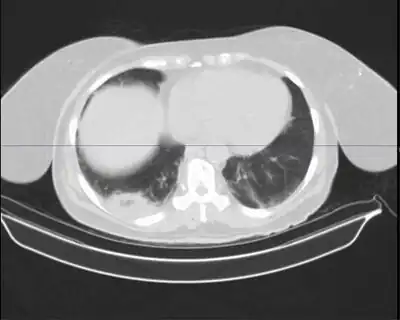

Mycobacterium nebraskense is a slow growing, yellow, pigmented mycobacterium[1] that was first isolated from human sputum at the University of Nebraska Medical Center, in Omaha, Nebraska, USA. Mycobacterium species are common causes of pulmonary infections in both humans and animals.

Mycobacterium nebraskense presenting as cavitary lung lesion